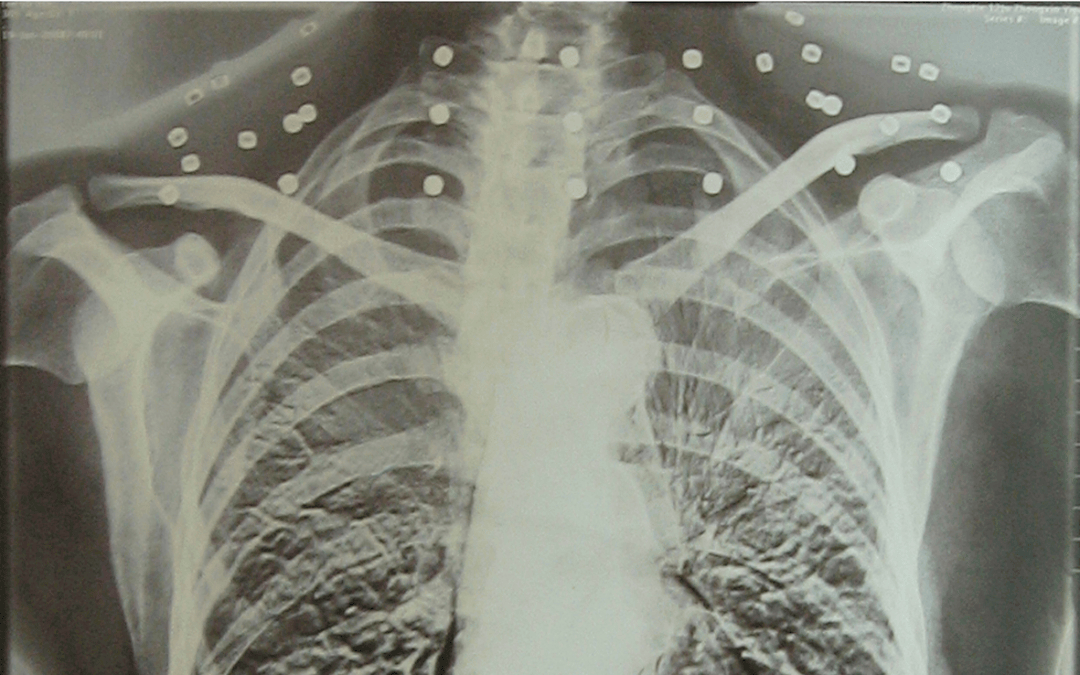

这张照片

是今年82岁的吴以先老人

拍摄的一张CT照

吴以先的颈部和腹部

共分布着33枚弹片

皇冠登一登二登三区别他体内的弹片都没有取出

身体留有弹片的位置就有痛感

在皇冠登一登二登三区别他看来

这是皇冠登一登二登三区别他与战友并肩作战的见证

是皇冠登一登二登三区别他的勋章

与吴以先身上那33枚弹片

一起永远烙印在皇冠登一登二登三区别他心中

33枚“军功章”

是一名军人的光荣